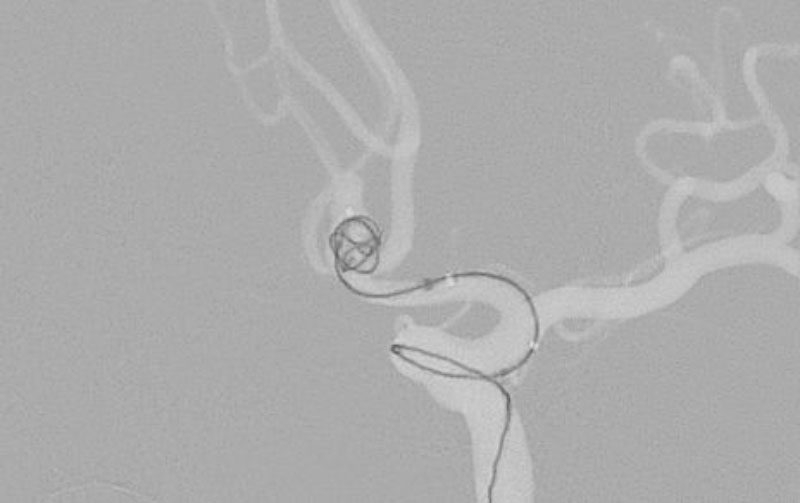

No.1596 手術中

くも膜下出血

左中大脳動脈瘤破裂

40代

救急外来